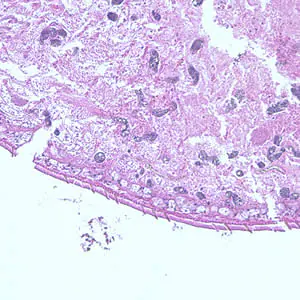

A patient complaining of intermittent symptoms including coughing up blood, fever, and other vague “flu-like” symptoms saw a physician. The patient reported working at a sushi restaurant and eating a raw crab on a dare (Figure A shows a crab similar to the one that the patient ate). Blood tests were ordered and results included peripheral eosinophilia of 10% and a history of bilateral pneumothorax (free air or gas in the pleural cavity). A biopsy yielded a cyst containing a structure 5 mm in length and 2 mm in width. Figure B (40×) and Figure C (100×) show a hematoxylin and eosin (H & E) stained section of the specimen. Figure D (400×) shows an object which measured 80-90 µm by 40-45 µm. Similar objects were found in low numbers in sections of lung tissue. What is your diagnosis? Based on what criteria?

Figure C